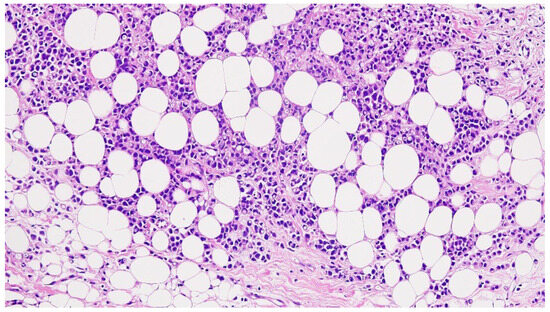

2.2. Imaging